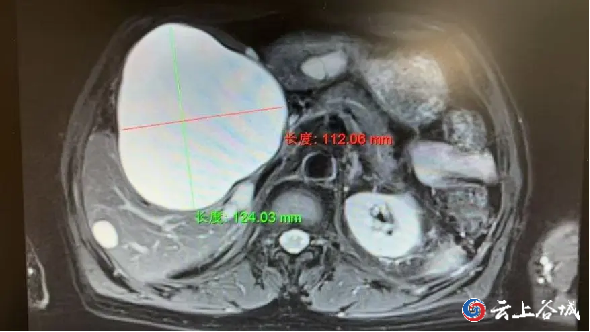

不久前,一名77岁的老年男性患者因“右上腹胀痛不适”来院。经检查确诊为“肝右叶巨大囊肿”,囊肿直径约10cm,已压迫周围脏器。

考虑患者年事已高,且合并高血压等基础疾病,传统开腹手术创伤大、恢复慢,风险较高。肿瘤科医疗团队反复研讨后,决定采用微创方案,开展CT引导下肝囊肿穿刺引流及硬化术。